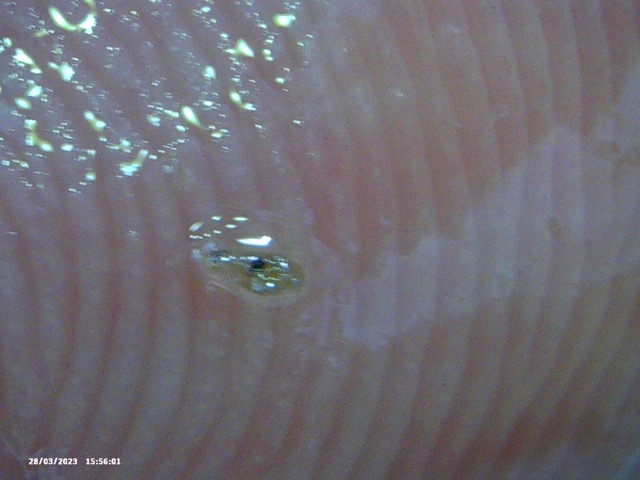

I showed him what I thought were reasonable compelling pictures of something that is clearly not right.

So I feel movement on parts of my body, then I get slight lumps and then I get these extremely large and sore white spots … and also, if I massage oil into those lumps I remove these objects.

So what are these objects with black things in?

‘Buried in the skin, and encased in these really hard objects that I’m extracting?’

Below is the selection of recent images that I showed him. In isolation they look like they could be ‘anything’ – but with the context of my described condition, and the consistency of objects being extracted, I thought this might, at a minimum be considered ‘not right’ and warrenting further investigation. Silly me.

Image Notes:

- That is my fingerprint in the background.

- All objects are recent and have been extracted over the last 2 weeks

- I simply cannot see some of these objects – however I can feel them, ROCK HARD.

- ‘Hair’ included for a sense of scale and also to help counter the lazy argument ‘That could be Hair embedded in those objects’ – mental gymnastics.

- This is a small selection of what I’m taking out of my skin where I am feeling movement, there are literally 100’s of these things. Imaging them become’s pointless as they are similar.

- Average Distance between fingerprint ridges is 0.15mm for a sense of scale.